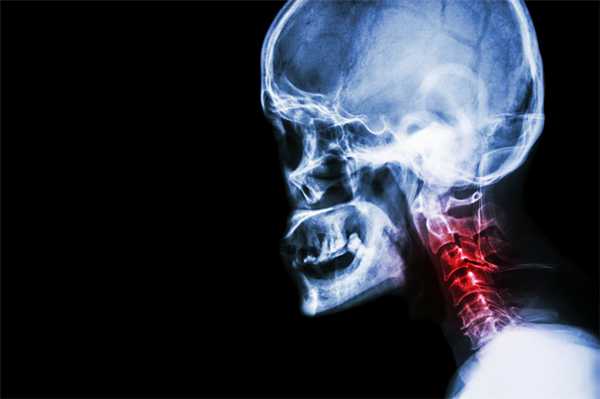

КТ поясничного отдела позвоночника. Деформирующий спондилоартроз. Умеренно выраженные дегенеративные изменения дугоотростчатых суставов